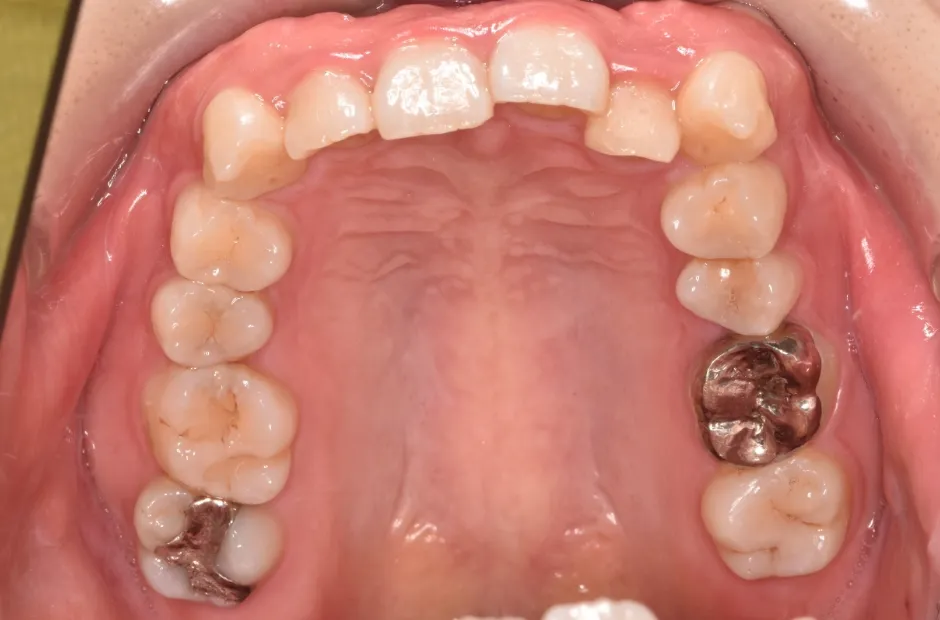

治療前